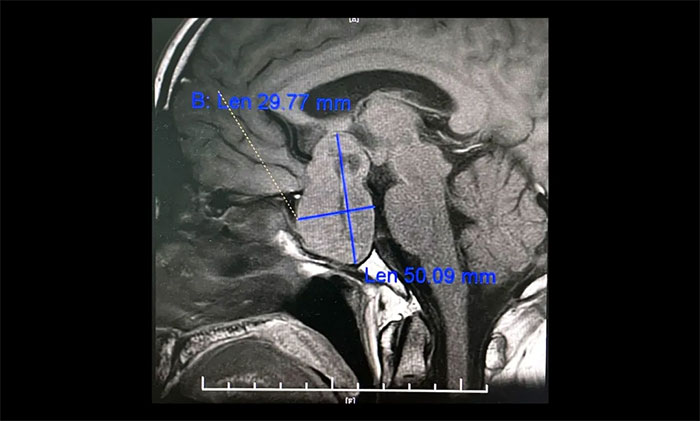

▲ 5公分巨大垂體瘤,呈“啞鈴”形,李士其教授團(tuán)隊迎難而上順利切除

李士其教授分析,對于病變已經(jīng)侵襲海綿竇,單純采用以往經(jīng)鼻入路或經(jīng)顱入路的術(shù)式均難以全切腫瘤,并且頸內(nèi)動脈損傷的風(fēng)險極大。如何將頸內(nèi)動脈損傷風(fēng)險降到最低,又能盡可能全切腫瘤?一般考慮采用經(jīng)蝶和經(jīng)顱聯(lián)合入路手術(shù)策略切除腫瘤。

目前聯(lián)合入路切除垂體瘤通常有兩種方式,一是采用聯(lián)合入路一次手術(shù)實現(xiàn)腫瘤全切除,二是分次手術(shù)以達(dá)到腫瘤切除的目的。李士其教授介紹,此類手術(shù),對患者的視力保護(hù)極其重要,對于巨大垂體瘤難以一次性手術(shù)切除的腫瘤,可以先行一次手術(shù),然后在數(shù)周或數(shù)月后執(zhí)行進(jìn)行二次手術(shù),即經(jīng)蝶和經(jīng)顱聯(lián)合入路分次手術(shù)策略。

李士其教授指出,因腫瘤組織多數(shù)較軟,鞍內(nèi)減壓后,鞍上及海綿竇內(nèi)腫瘤?上虬皟(nèi)塌陷。如術(shù)中塌陷不滿意可暫予觀察,一般1-3月后復(fù)查腫瘤可大部落入鞍內(nèi),可再次經(jīng)蝶手術(shù)進(jìn)一步切除。如仍不塌陷可考慮開顱手術(shù),此時開顱手術(shù)難度及風(fēng)險降低,而鞍底組織已愈合,一般不必?fù)?dān)心腦脊液漏。